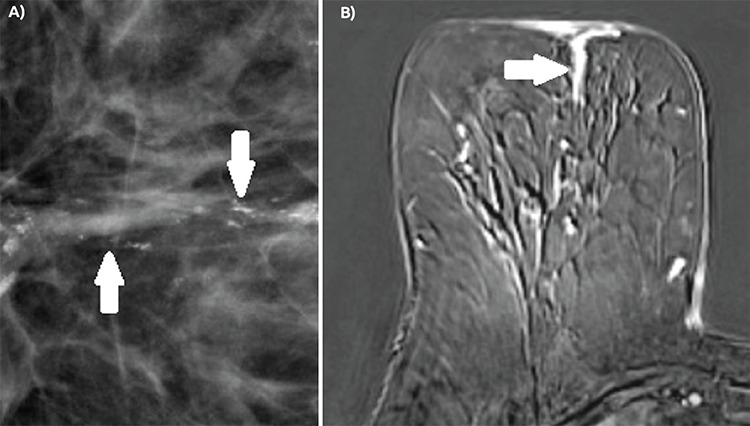

Results: Among the lesions, 44 were double HRc-positive (ER and PR-positive), 13 were single HRc-positive (ER-positive and PR-negative or ER-negative and PR-positive) and 22 were double HRc-negative (ER and PR-negative). The presence of symptom (p = 0.029), the presence of comedo necrosis (p = 0.005) and high histological grade (p<0.001) were found to be associated with ER and PR negativity. Amorphous microcalcifications were more commonly observed in the double HRc-negative group, while linear calcifications were more prevalent in both double and single HRc-positive groups (p = 0.020). Non-mass enhancement (NME) with a linear distribution was significantly more common in double HRc-negative lesions (38%), and NME with a segmental distribution in both double (43%) and single (50%) receptor-positive lesions (p = 0.042). Evaluation of DWI findings revealed that a higher lesion-to-normal breast parenchyma apparent diffusion coefficient (ADC) ratio statistically increased the probability of HRc positivity (p = 0.033).

Conclusion: Certain clinicopathological, mammography, and MRI features, along with the lesion-to-normal breast parenchyma ADC ratio, can serve as predictors for HRc status in DCIS lesions.